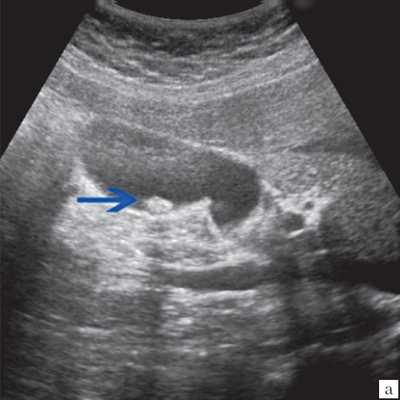

(Левый) На продольном УЗ срезе визуализируется желчный пузырь, содержащий не отбрасывающий тени опухолевидный сладж.

(Правый) Положение пациента на боку. На продольном срезе в просвете желчного пузыря определяются подвижные множественные флотирующие эхо-сигналы. Обратите внимание на почти спавшийся желчный пузырь и выраженное утолщение его стенки.